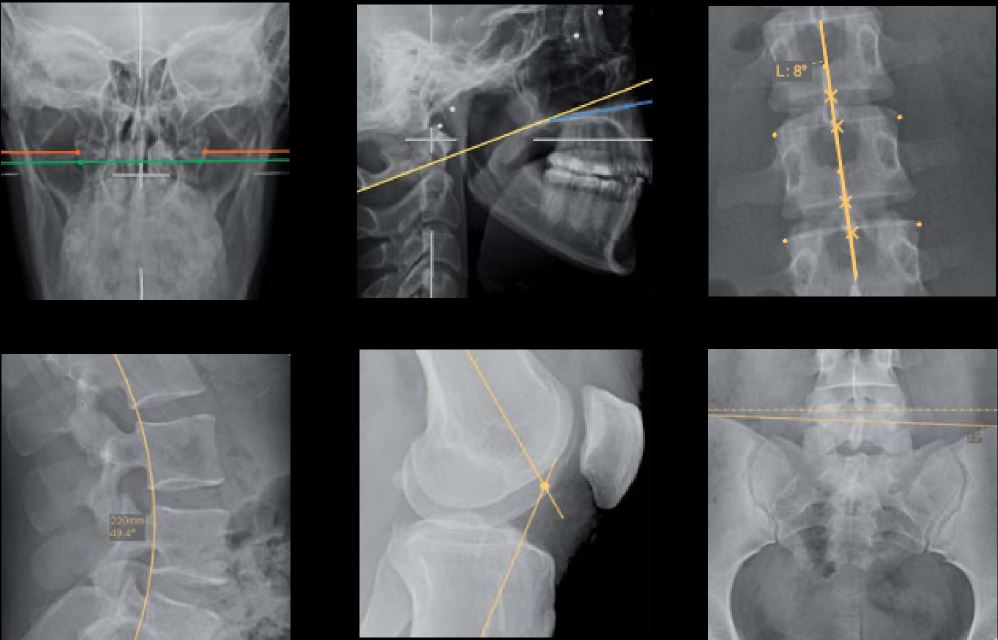

Vous pourrez réaliser vos diagnostics directement sur la console en profitant de traitement d'images puissants et d'une palette d'outils complète (annotations, mesures, zooms, filtres,...) .

Un mode Stitching simple d'utilisationReconstruction automatique ou manuelle à partir de trois clichés pour les examens de la colonne vertébrale ou des membres inférieurs. |